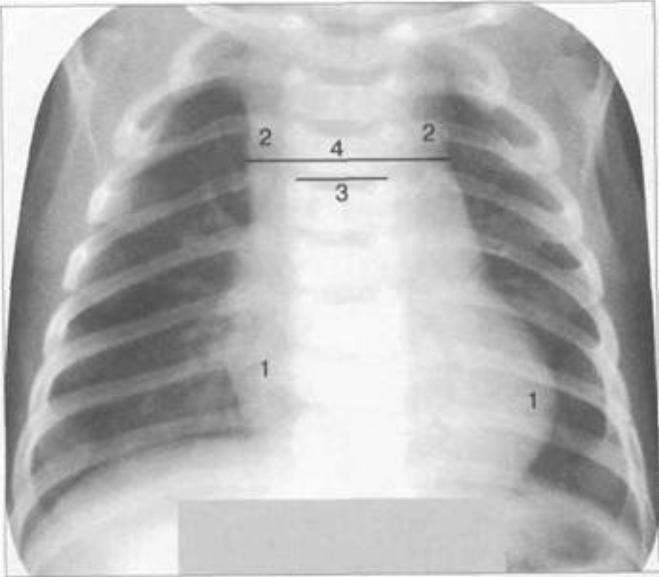

Тимомегалия: что это такое и как проявляется